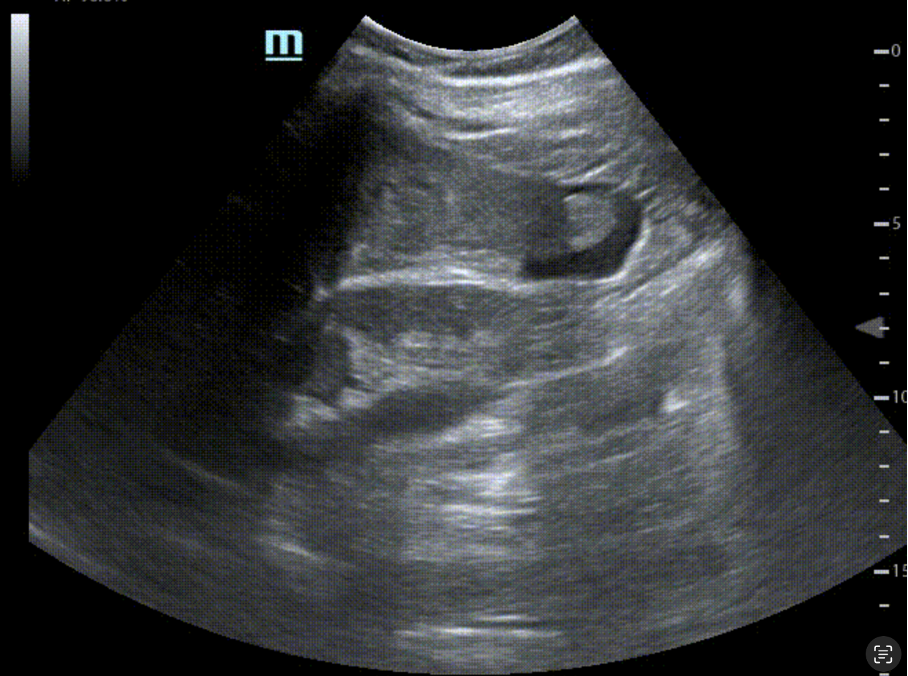

Recessus hépatorénal (espace de Morison)

Fenêtre sous-costale droite avec sonde convexe : on recherche un liseré anéchogène entre le foie et le rein droit. Cet espace est très sensible aux faibles volumes d’épanchement et offre souvent une image caractéristique dès quelques centaines de millilitres au contact du foie.